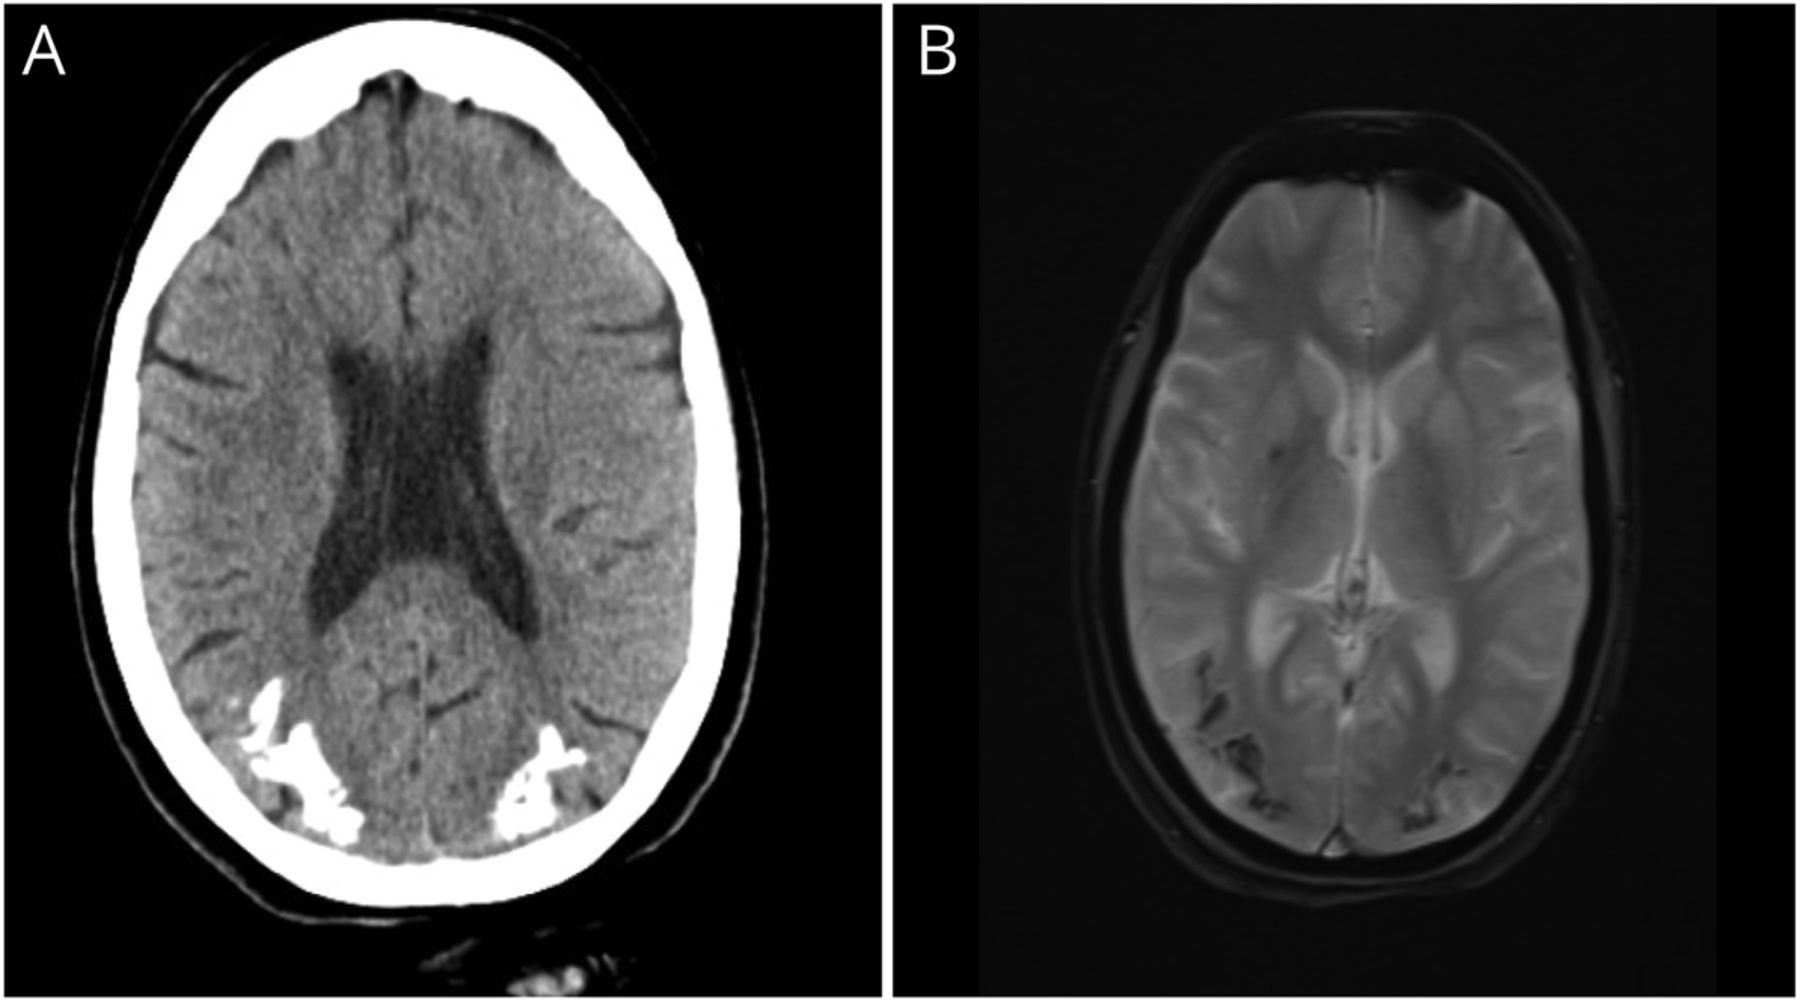

一个18岁的女人面对难治性癫痫时开始的10年。没有其他疾病的药物的使用历史,辐射,或者神经皮肤耻辱。她的CT扫描和核磁共振(GRE) (图中,A和B显示在parieto-occipital地区双边皮层和皮层下钙化。根据她的影像学表现,腹腔疾病、癫痫、脑钙化(CEC)综合症1,2被认为是。这证实了高antigliadin IgA的存在(7.16 U /毫升),免疫球蛋白(36.12 U /毫升)和免疫球蛋白g组织转谷氨酰胺酶(645 U /毫升)的水平。发作脑电图显示广义排放。差异是Sturge-Weber综合症(慢波睡眠),先天性叶酸吸收不良,用甲氨蝶呤治疗和antifolate,放射治疗。慢波睡眠被排除在外,因为缺乏面部痣,大叶性萎缩,MRI上皮层下钙化。与沉默的乳糜泻病人CEC综合症。无谷蛋白饮食和抗癫痫药物推荐。她在后续控制发作。